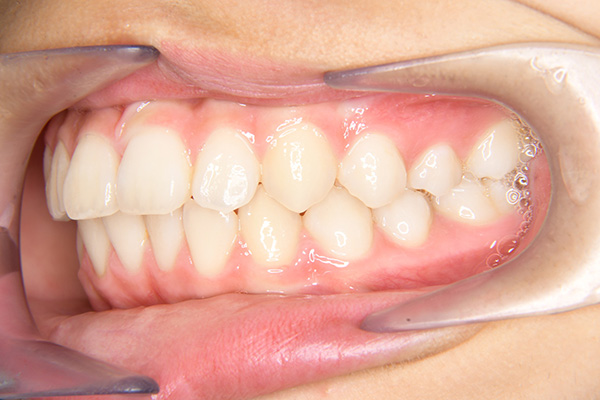

主訴 出っ歯 診断名 アングルⅡ級1類

初診時年齢 7歳0ヵ月 性別 動的治療期間 28ヵ月

口腔内所見 over jet 7.5mm,over bite 3.5mm,大臼歯関係はⅡ級 。Hellmanのdental ageはⅢAであり上突咬合を呈していた。